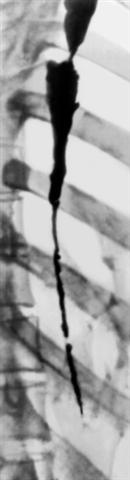

Рис. 4. Рентгенограмма тотальной послеожоговой стриктуры пищевода.